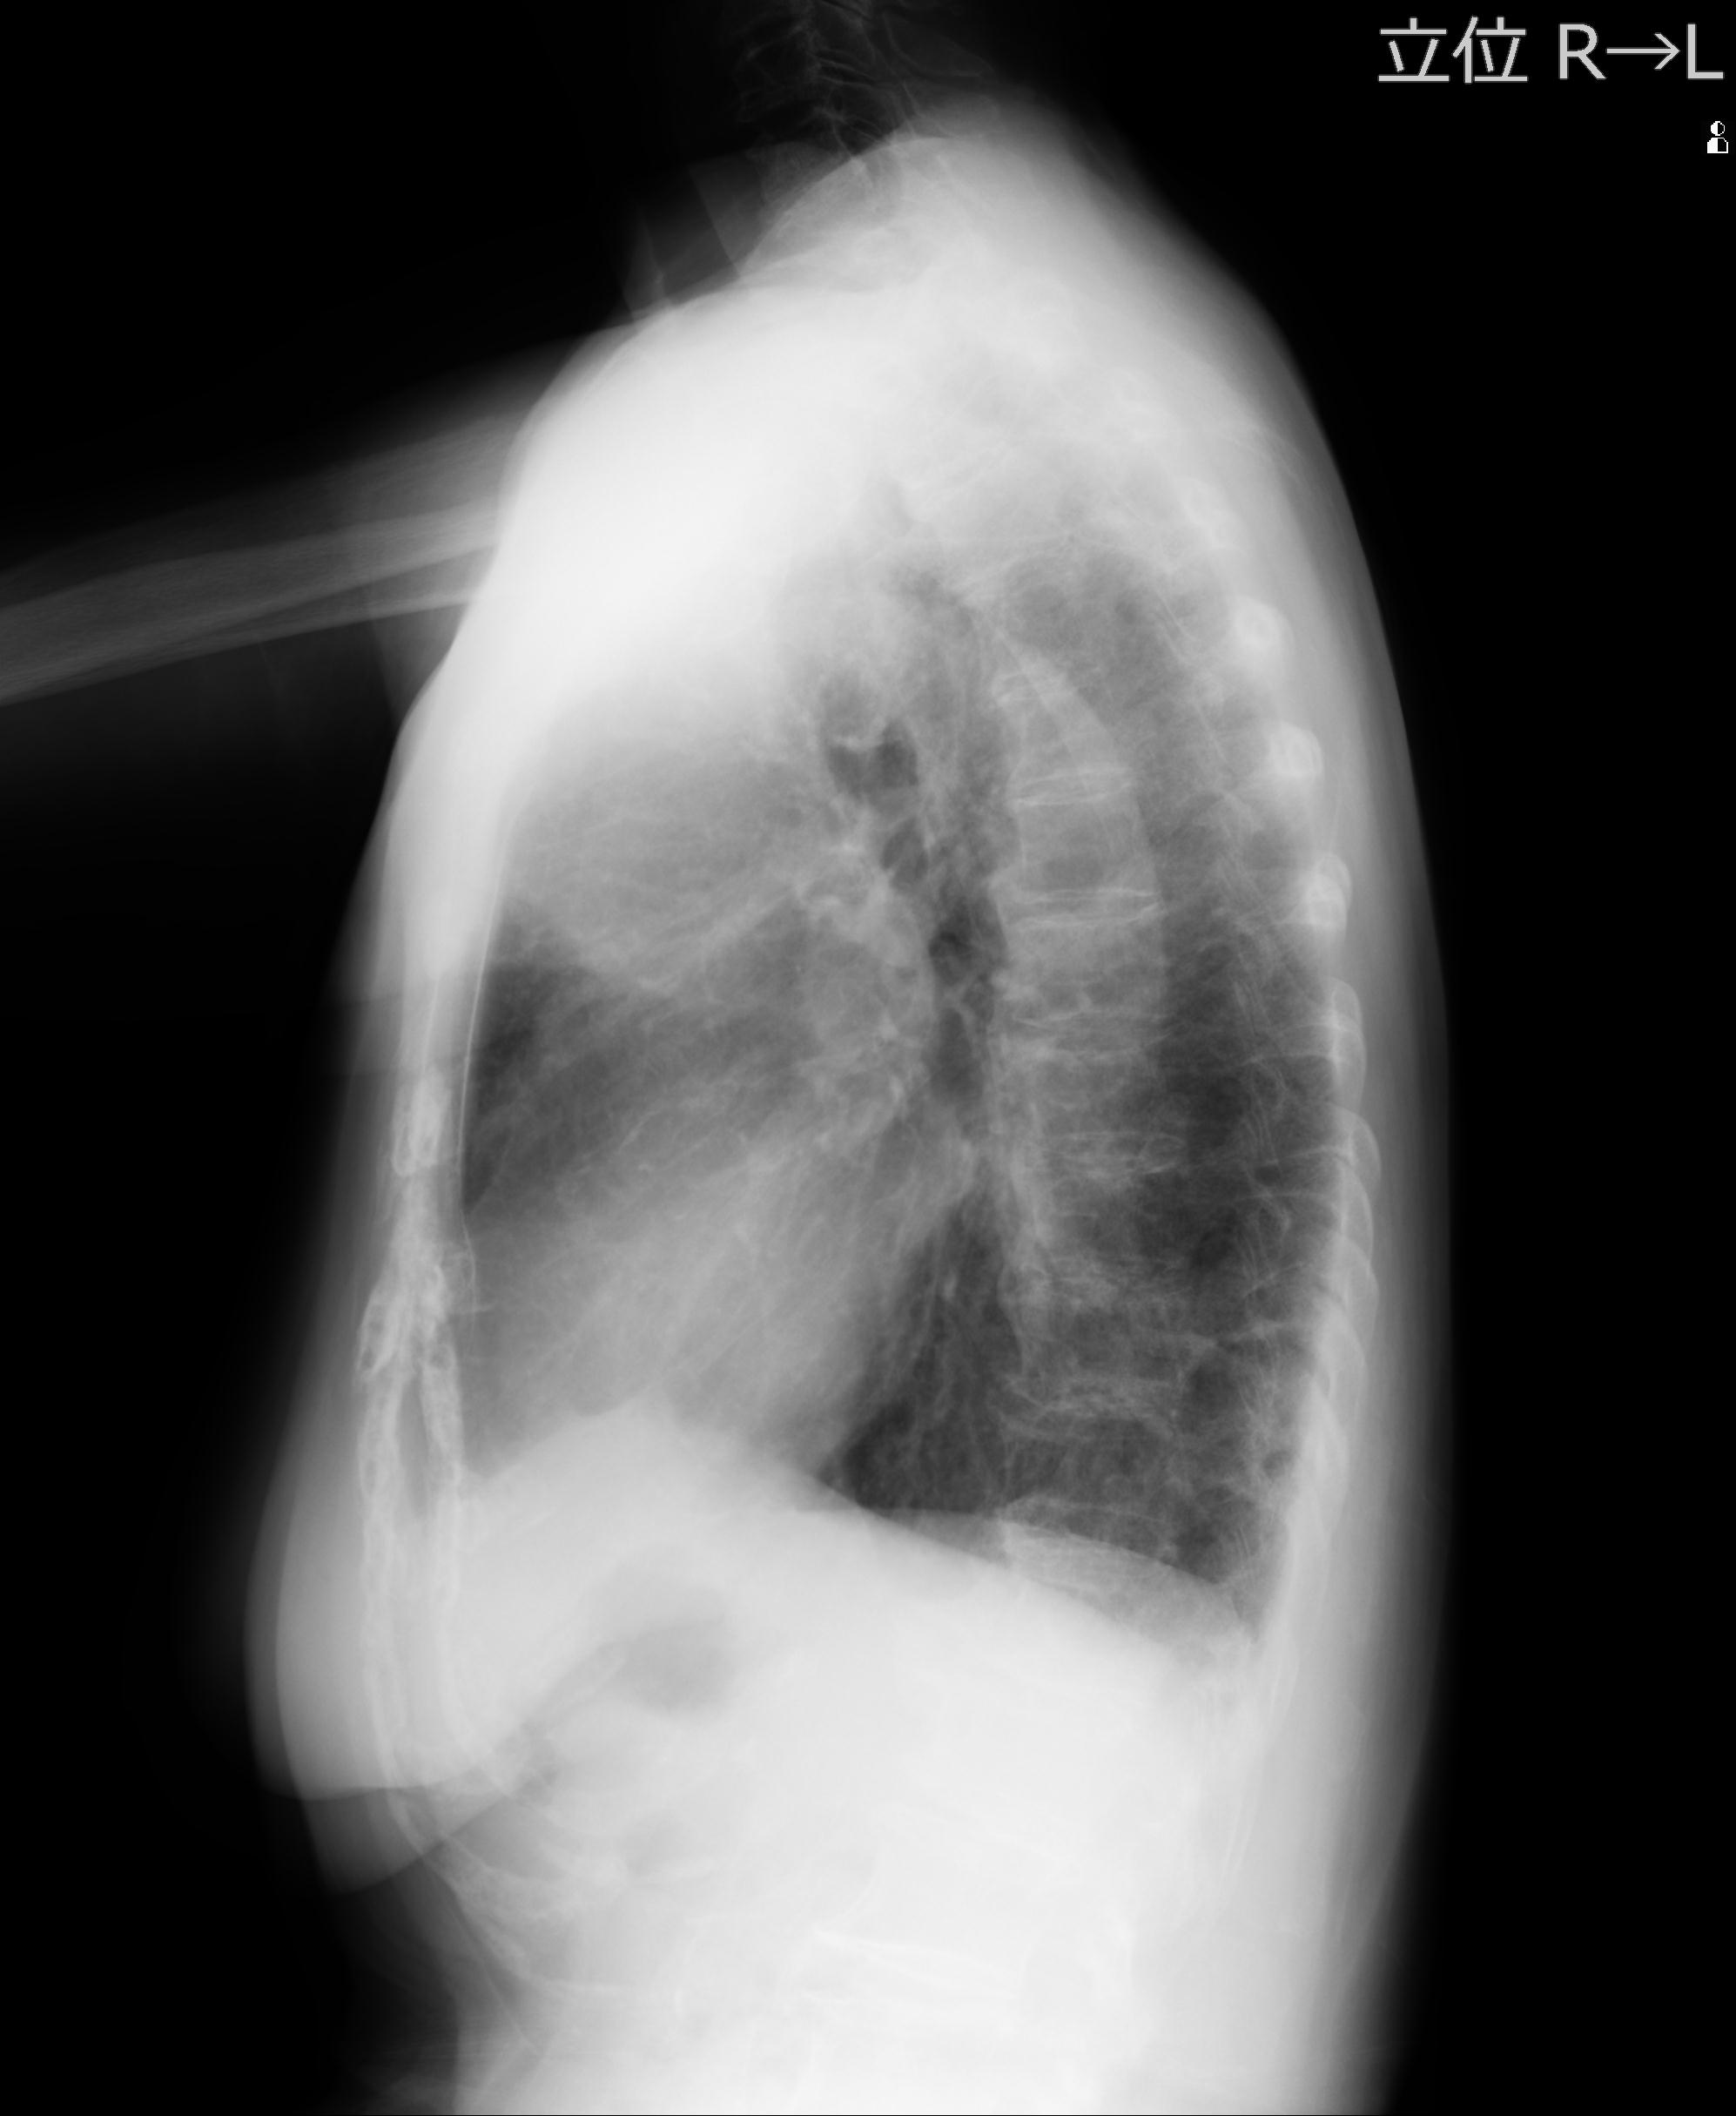

60058 3/9 11/4 右肩 2R+MRI 73歳男性 肩腱板損傷